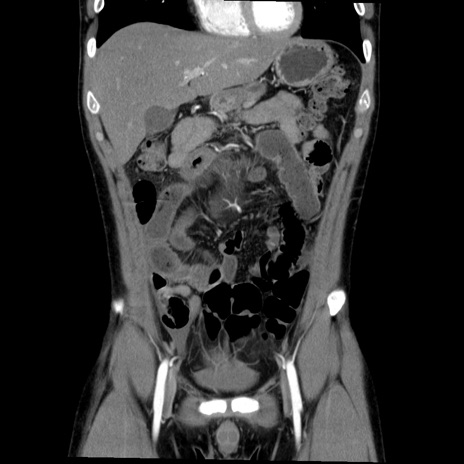

症例36(冠状断像)

【症例】20歳代 男性

【主訴】心窩部痛

【現病歴】今朝より上腹部痛あり。一旦軽快していたが再度出現したため救急要請。昨日夕に白身の魚を含む刺身を食べた。

【身体所見】BP 136/89mmHg、HR 74/min、BT 37.0℃、腹部:膨満、軟、心窩部に圧痛あり。反跳痛なし、筋性防御なし、腸雑音やや亢進あり。

【データ】WBC 17700、CRP 0.48